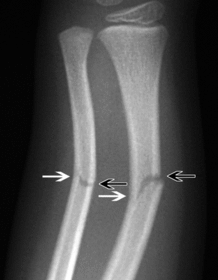

AP no rotation radius and ulna partially superimposed

AP Lateral Rotation separation of radius and ulna

AP Medial Rotation superimposed radius and ulna

A. Supination B. Pronation